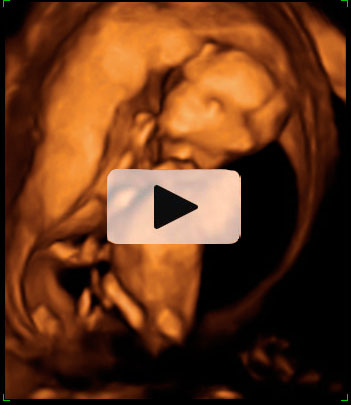

Aspecto de un bebé de 12 semanas tomado en ecografía 3D.

Se pueden apreciar con toda claridad la cabeza (aún más grande en proporción, que el resto del cuerpo), el tronco, las extremidades y el cordón umbilical. El niño ya se apoya con la espalda en el útero materno, lo que facilita la exploración por parte del ecografista.